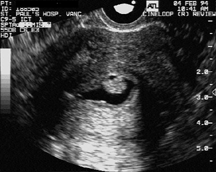

Polip tanısı büyük oranda transvajinal ultrasonografi ile konur. Ancak yalancı polipler ile karışabilir. Rutin ultrason incelemesi yerine rahim iç boşluğunu daha iyi gösteren sulu ultrasonografi (sonohisterografi) polip tanısında en etkili yöntemlerden birisidir. Rutin transvajinal ultrasonografinin polipleri saptamadaki duyarlılığı %66 iken sonohisterografinin duyarlılığı %100’dür.

Sonohisterografide endometrial polipin görünüşü

Polip tanısında altın standart histeroskopidir. Direkt olarak gözle görülen polip aynı anda alınarak tedavisi de gerçekleştirilmiş olur.